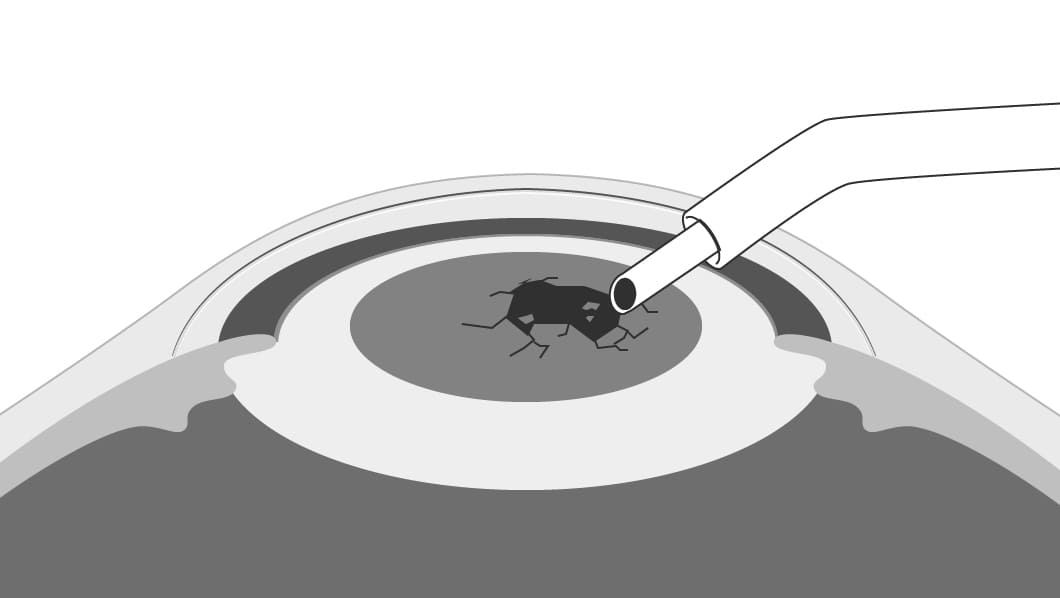

- 2濁った水晶体を砕いて吸い出します。

-